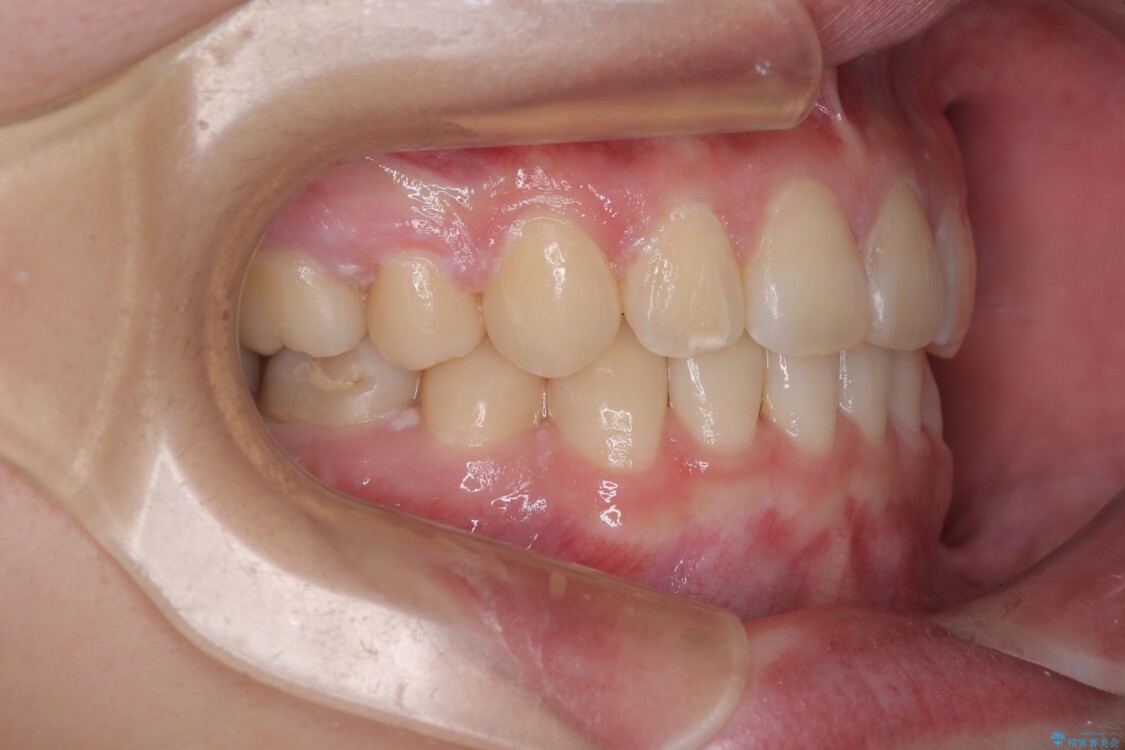

治療後

• 転勤でも安心して治療継続 抜歯スペース閉鎖と深い噛み合わせ改善のワイヤー矯正 治療後画像